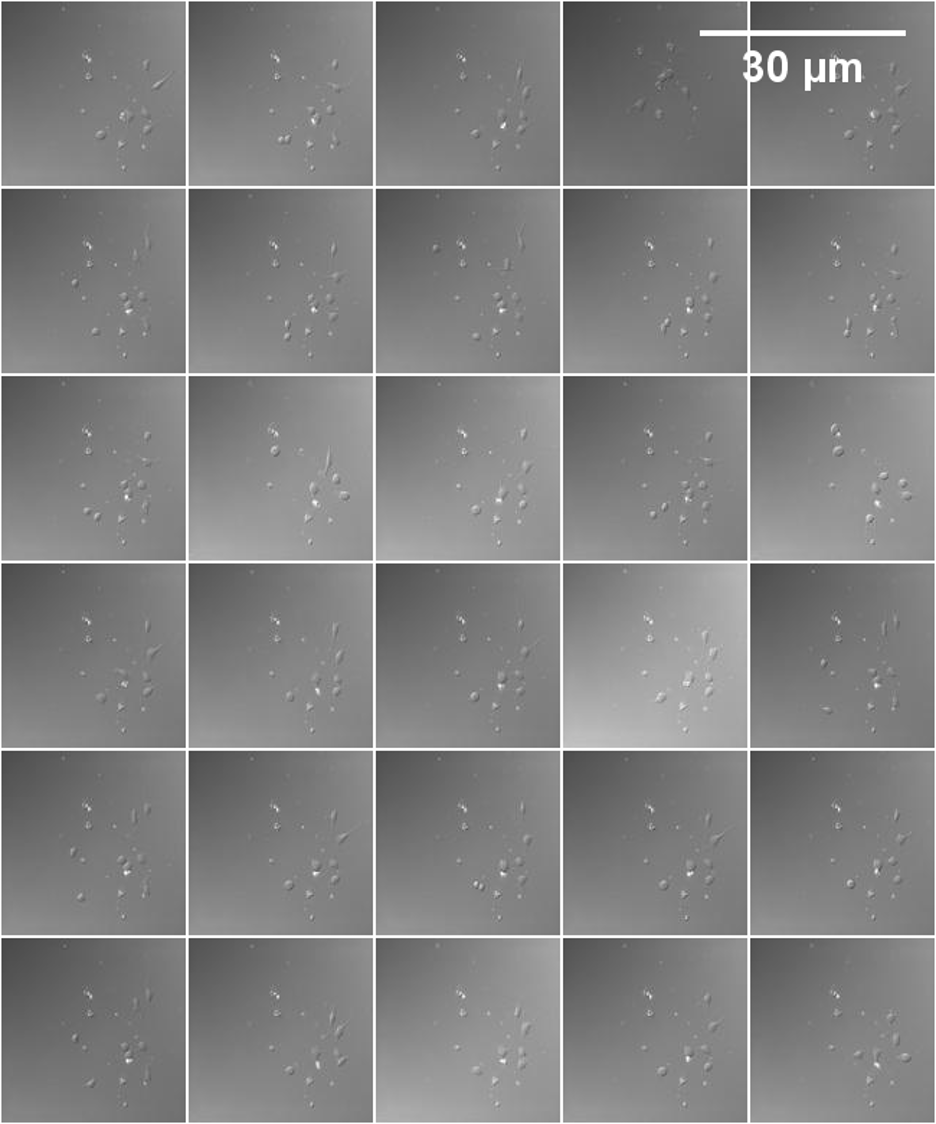

Figure S13: A sample of the final images created from the proposed method (128×\times128 for each sample) using the Neural dataset.

Refer to caption

Figure S14: A sample of the final images created from the real images (128×\times128 for each sample) using the Neural dataset.